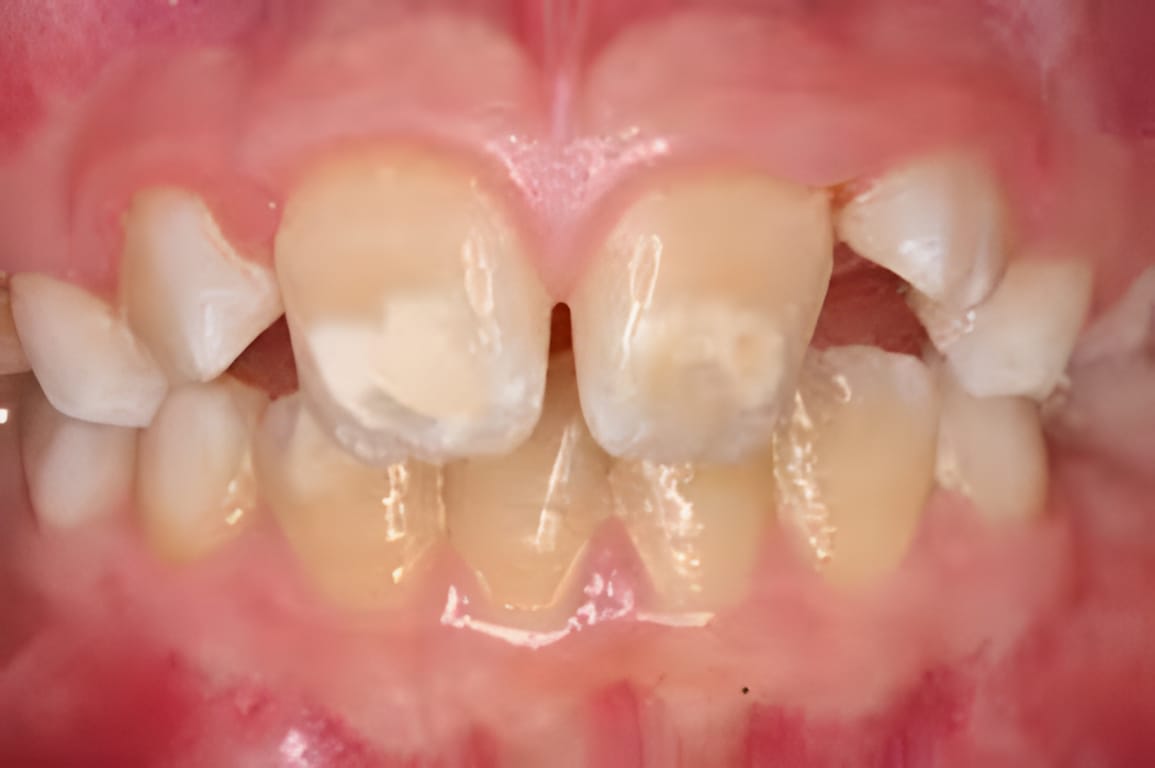

Kreidezähne, auch Molaren-Inzisiven-Hypomineralisation (MIH) genannt, sind eine Zahnschmelzbildungsstörung. Dabei ist der Zahnschmelz unzureichend mineralisiert, wodurch er weicher, poröser und bruchanfälliger wird. Betroffen sein können sowohl das bleibende Gebiss als auch das Milchgebiss. Typisch sind umschriebene, weissliche bis gelblich-bräunliche Verfärbungen. Der geschwächte Schmelz kann leichter ausbrechen und die Zähne reagieren oft empfindlich.

- Flecken/Verfärbungen (weiss, gelb, braun) mit klaren Rändern

- Rascher Substanzverlust: Schmelz bricht beim Kauen oder Putzen ab